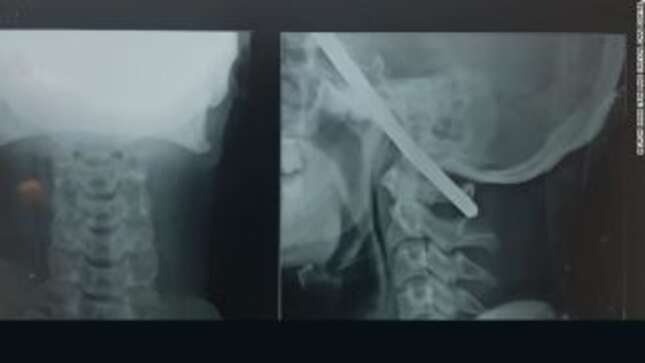

Al parecer, después de que lo trasladaran al Hospital B.J., en la ciudad de Gondia, los médicos pudieron retirarle cuidadosamente la barra y evaluar el daño. Lo que encontraron fue ciertamente impactante. El diagnóstico encontró que la barra había ingresado en el cráneo a través de la región temporal derecha de su cerebro, y que había salido a través de la región frontal izquierda, sin embargo, de alguna forma el pedazo de metal había evitado atravesar zonas que le causaran un daño irreversible.

Tal y como han contado los doctores, la extracción del objeto se realizó con extrema precaución y requirió de un gran equipo de neurocirujanos, todos dirigidos por el doctor Pramod Giri. Una cirugía que tomó 90 minutos, una hora y media de tensión máxima, ya que se debía realizarse lo más rápidamente posible una vez que Bahe comenzó a entrar en una fase de hipertensión, esperada aunque peligrosa.

La vara estaba a escasos milímetros de la ruptura letal de los principales canales de sangre del paciente hacia el cerebro. Esto también explica por qué casi no hubo sangre durante el incidente. Dar anestesia al paciente en tales casos es difícil. Hicimos lo correcto al colocar la intubación para mantener canales vitales en el cerebro durante la operación. Realicé la cirugía con toda precaución para que no se produzcan daños en las estructuras circundantes.